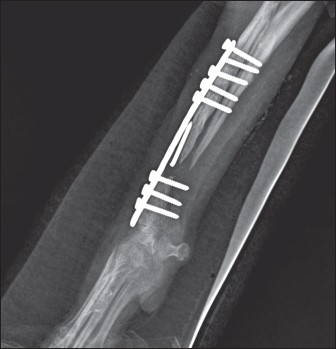

То harvest the autogenous cortical graft, a caudal approach to the contralateral ulnar diaphysis was used (Fig. 2). The subcutaneous tissue was bluntly dissected, and thereafter retraction was maintained using Gelpi retractors. A Hohmann retractor was placed between the ulna and radius to prevent iatrogenic damage to the radius. A 4.8 cm long bone segment of the ulnar diaphysis was removed by means of an oscillating saw. The ostectomy and periosteum were removed en bloc and transferred into the surgical gap of the right radius. At both ends of the cortical autograft, a cancellous graft soaked with 1,000 IU recombinant human erythropoietin (Binocrit®, 2000 IU, Sandoz GmbH, Kundl, Austria) was applied for optimization of osteoinduction and angiogenesis. To collect the cancellous graft, a small incision was made over the craniolateral aspect of the greater trochanter. A 3.5-mm hole in the proximal humeral metaphysis was created with a drill bit and a bone curette was used to harvest the cancellous graft. Then, it was inserted into the recipient site as soon as possible to minimize cell death. After proper alignment of bone fragments, they were fixed with a dynamic compression plate (1.5 mm thickness) and 8 cortical screws: 2 in the distal radial fragment, 3 in the cortical graft, and 3 in the proximal radial fragment (Fig. 3). The intradermal layer was closed with an absorbable monofilament suture material (PDX, 3-0, VetSuture, France), followed by non-absorbable skin sutures (Nylon, 3-0, Kruuse, Denmark).

Fig. 3. Mediolateral radiograph of antebrachial bones after the revision surgery. Left: the ulna of the healthy thoracic limb after harvesting of the cortical autograft. Right: fixation of the cortical autograft with dynamic compression plate.